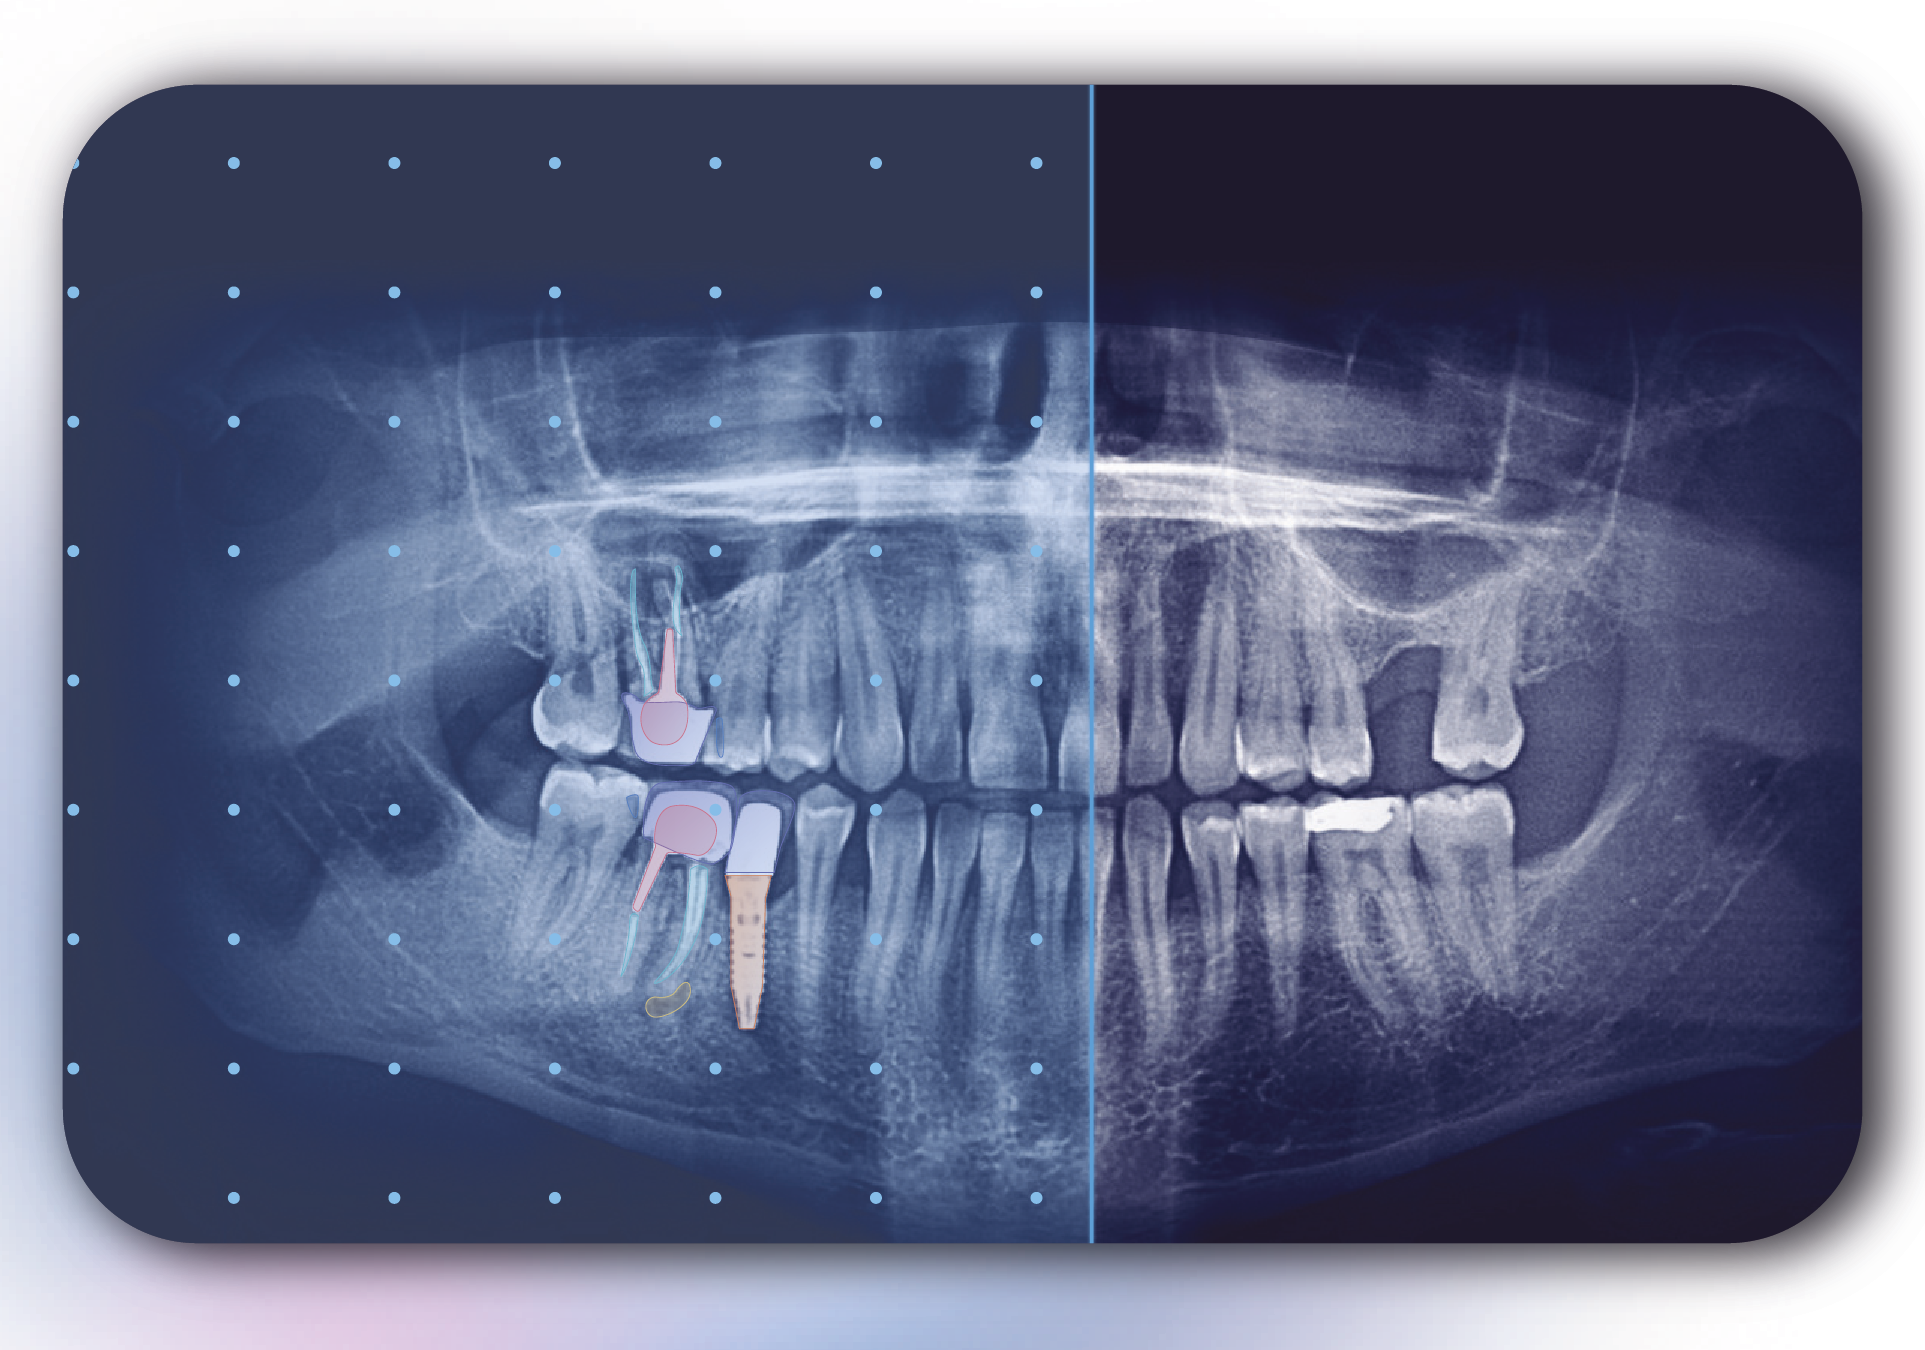

Allisone es una herramienta de comunicación con el paciente que utiliza IA para resaltar elementos de las radiografías dentales que permiten a los pacientes visualizar y comprender la atención dental que necesitan. (Imagen: Allison)

Allisone es un software que utiliza tecnología de inteligencia artificial, aprendizaje profundo y visión por computadora, mediante la cual reconoce elementos en una radiografía dental de la boca. Los resultados se visualizan mediante una interfaz simple e intuitiva que ayuda a los dentistas a mostrar los elementos en la radiografía a través de un código de colores.

El propósito principal de esta funcionalidad es apoyar visualmente la explicación del dentista sobre los tratamientos que necesita paciente. Allisone produce instantáneamente el informe radiográfico, el plan de tratamiento y las ilustraciones y agrega hojas educativas basadas en el tratamiento seleccionado por el dentista. Estos elementos se pueden enviar al paciente o imprimir para dárselo en mano. Allisone se puede integrar con otros softwares comerciales y es accesible desde cualquier computadora en la consulta o clínica.